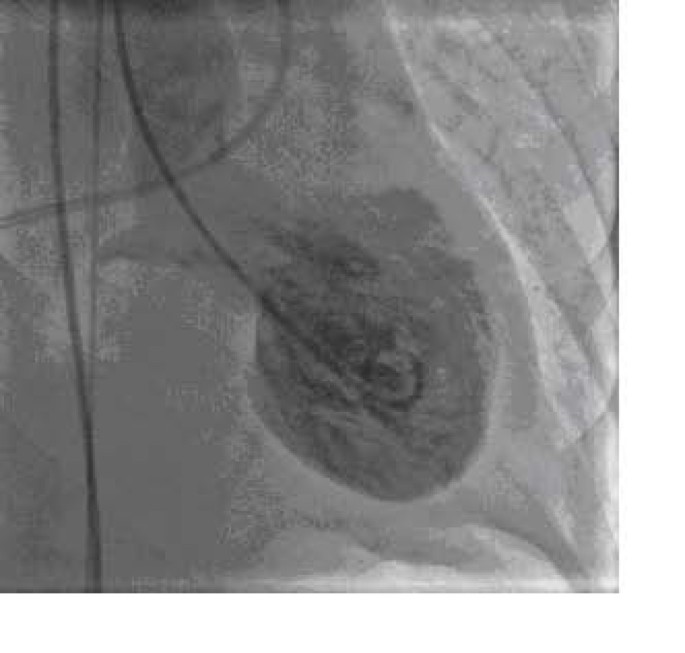

She was subsequently transferred to hospital with invasive cardiac catheterization facilities for emergency cardiac catheterization Coronary angiography revealed non obstructive coronary arteries (Figure 2). Left ventriculogram showed systolic dysfunction of the left ventricular apex and mid-ventricle, with hyperkinesis of the basal left ventricular segments and LVOT blood flow gradient of 58 mmHg and a 2+ mitral regurgitation (Figure 3).

Left ventriculography during end-systole showing systolic dysfunction of the left ventricular apex and mid-ventricle, with hyperkinesis of the basal left ventricular segments (A). This finding on left ventriculography resembles the look of a Japanese takotsubo pot which was traditionally used for catching octopus.